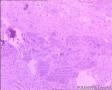

腱鞘囊肿?

性别年龄65临床诊断

一般病史肘部肿物半月

标本名称切除组织

大体所见手术所见:3*3cm囊性肿物,内有淡黄色液体 送检碎组织多块,内外壁光滑,质软

绒毛结节性滑膜炎。

结合2号切片符合绒毛结节性滑膜炎

腱鞘囊肿

滑囊囊肿

典型的滑膜囊肿